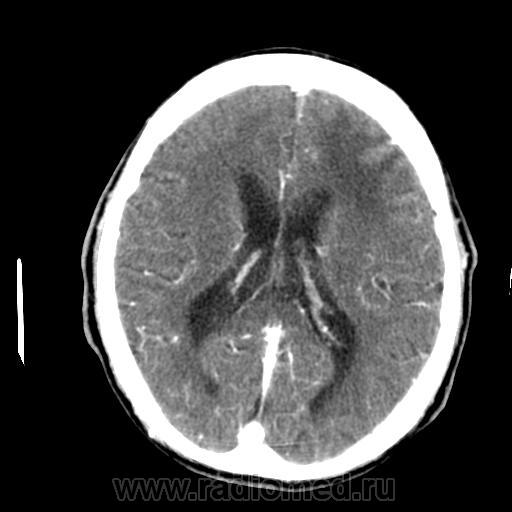

4-я - отсроченн. (5мин).